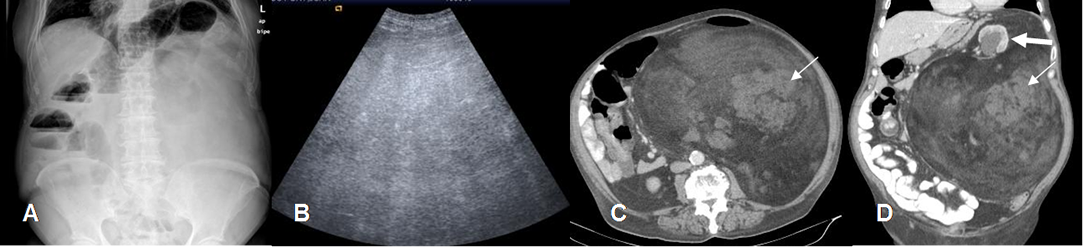

Fig 166 B. Liposarcoma bien diferenciado.

A: Rx AP. Efecto de masa en el hemiabdomen izquierdo, que desplaza las asas.

B: Ecografía. Lesión heterogénea y de consistencia sólida.

C: TAC axial y D: TAC reconstrucción coronal. Gran masa retroperitoneal, con densidad de predominio graso. Se encuentran imágenes redondeadas y mas densas, por tejido fibroso. (Flechas delgadas). Desplazamiento y mal-rotación del riñón izquierdo, el cual está dilatado por compresión del uréter. (Flecha gruesa).